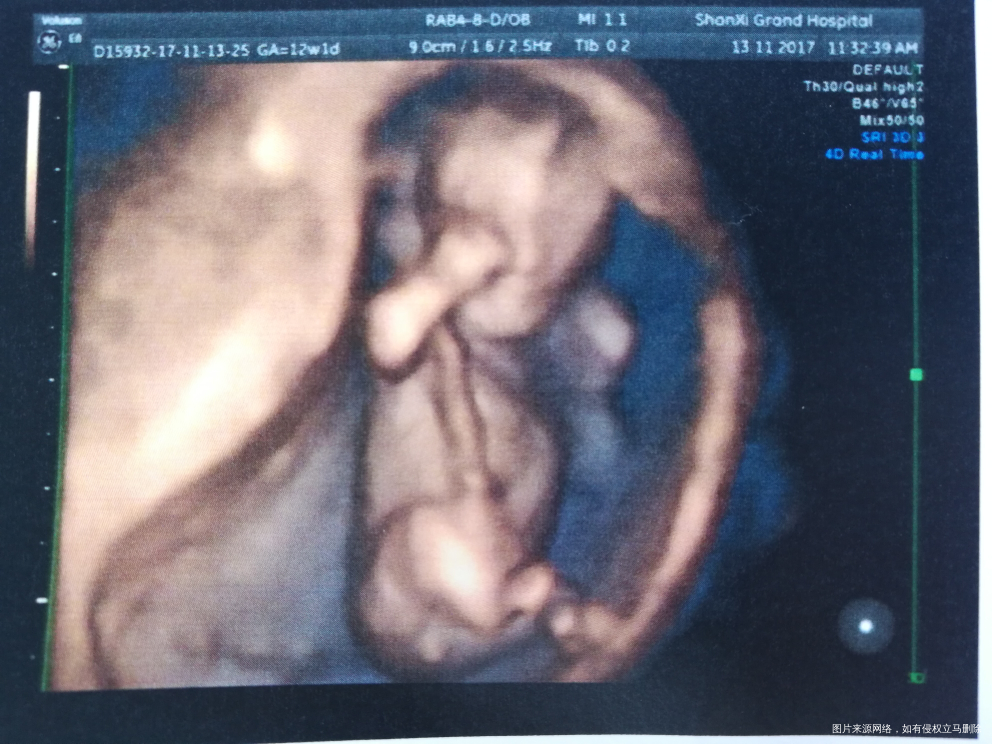

照的好清楚啊

看屁股底下圆圆的像蛋蛋!!

第二张图底下是不是小鸡鸡[大笑][大笑]

照的好清楚,宝宝好可爱。接产检顺利通过。

好像是男孩,下边有东西[大笑][大笑]